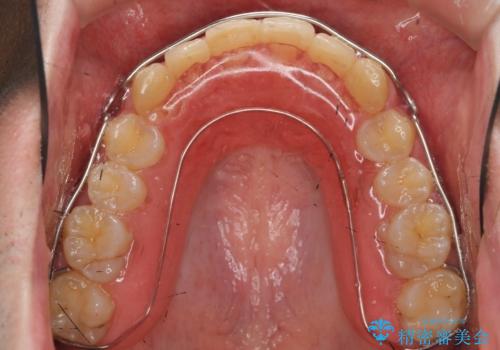

ガタつきの大きい前歯 インビザラインによるマウスピース矯正治療

- ガタつきの目立つ前歯の改善を求めて来院されました。

上顎前突、がたつきを改善すべく上顎臼歯の後方移動・ディスキングを行い歯並びの改善を計画します。

食事・歯ブラシ時以外の時間にしっかりとマウスピースを装着していただけたのでガタつきは大きく改善し良好な歯並びを得ることができました。